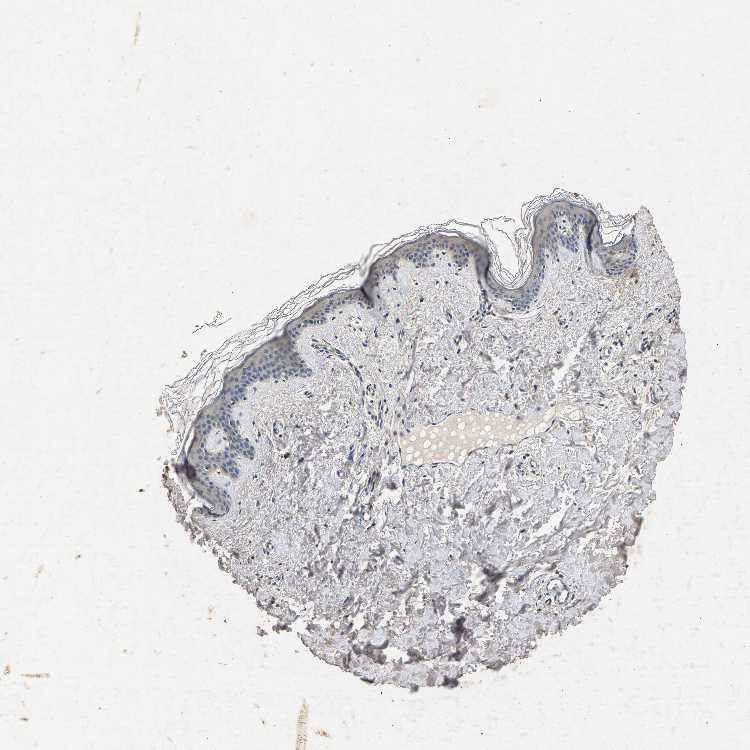

SKIN 1 - Antibody stainingi

Antibody staining in the annotated cell types in the current human tissue is reported as not detected, low, medium, or high, based on conventional immunohistochemistry profiling in selected tissues. This score is based on the combination of the staining intensity and fraction of stained cells.

Each image is clickable and will lead to virtual microscopy that enables deeper exploration of all samples and also displays staining intensity scores, fraction scores and subcellular localization as well as patient and tissue information for each sample.

Antibody CAB022645

Langerhans Not detected

Fibroblasts Low

Keratinocytes Low

Melanocytes Not detected